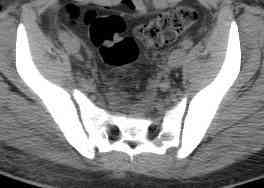

Уважаемые коллеги! опять вопрос по повреждению таза. Больной получил производственную травму 10 дней назад - удар балкой около 3 тонн в область верхней трети правого бедра и лона.

Был диагностирован перелом "типа бабочки" и повреждение уретры. Сделана цистостома. У насв отделении 3 дня. Имеется огромная флюктуирующая гематома с "галифе"-образной деформацией обеих бедер. Пнкционно эвакуировали в несколько приемов из подфасциальных полостей на бедрах около 3 литров геморрагического отделяемого с последующей эластической компрессией. При пункциях выявлено сообщение полостей на бедрах - видимо через поравннуюдиафрагму дна и полость таза - при удалении крови справа уменьшался объем левого бедра. Какой то активности проявялять покабоимся - аппаратная фиксация через отслоенные ткани представляется чреватой нагноением, открытая фиксация в условиях такой гематомы тоже не радует. Хотелось бы услышать ваше мнение

можно полечить в 2 этапа:как правило в области гребней гематомы все же не бывает, если гребни "свободны", то можно ограничиться на первом этапе передней рамой, вводя стержни через них (повреждение ротационно-нестабильное), затем после лечения отслаивающего повреждения Morel-Lavallee, выполнить открытую репозицию, внутреннюю фиксацию, возможно вместе с урологами. Тактику возможного лечения этой

С моей точки зрения, бояться аппарата внешней фиксации не надо. Более того, он абсолютно показан, и чем раньше, тем лучше.